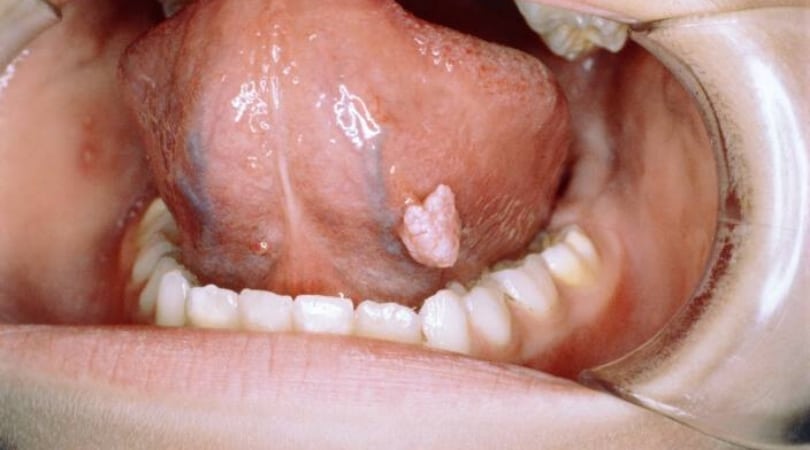

- Появление множественных кондилом и папиллом (в частности, на половых органах).

Папиллома в ротовой полости, как один из первых признаков ВИЧ у мужчин, фото: